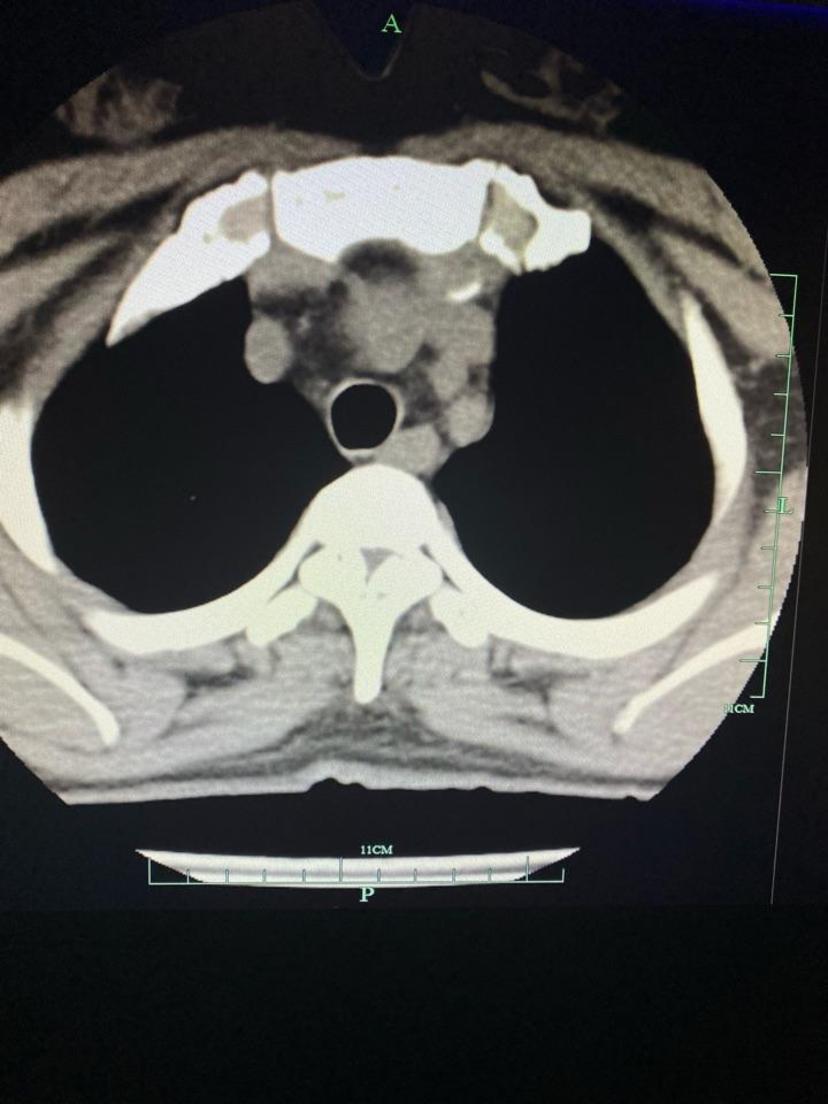

术后CT显示骨化物彻底去除,恢复正常椎管容积

术后CT平扫显示骨化物彻底去除,减压充分